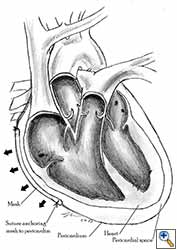

Video 1 depicts a pericardial reconstruction with Marlex after a right completion pneumonectomy with pericardiectomy for lung adenocarcinoma (see also Figure 1). The technique of pericardial reconstruction after the resection of invasive mediastinal tumours is illustrated in Figures 8a-c). Video 2 depicts a pericardial reconstruction with Mersilene mesh after the resection of a malignant thymoma invading the anterior pericardium (see also Figure 4b). The technique of right pericardial reconstruction after extrapleural pneumonectomy is illustrated in Figures 9a and 9b). Video 3 depicts a pericardial reconstruction using Gore-Tex Dual Mesh after a left extrapleural pneumonectomy (see also Figure 3). Care must be taken to prevent constriction (Figure 10).

| Figure 10a: Concept of geometric pericardial reconstruction. | Figure 10b: Non-geometric pericardial reconstruction can lead to cardiac tamponade. |

- The pericardium must be reconstructed in a geometric, tridimensional fashion to avoid constriction (Figures 10a, 10b).